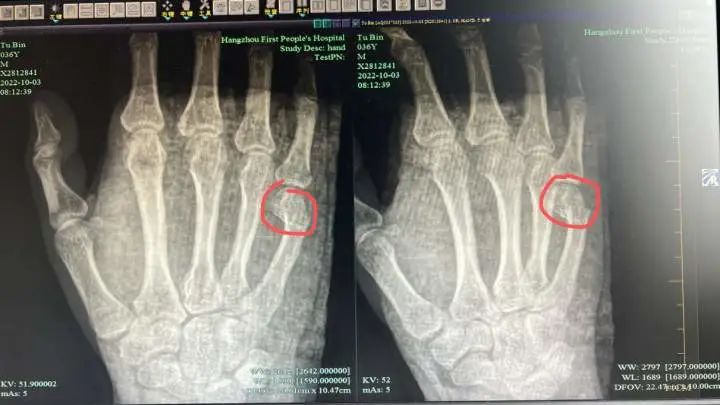

X光检查提示:吴先生的右手第5掌骨远端骨折,断端移位明显,需住院治疗。“没想到挥了一拳头,竟把自己手掌捶骨折。”

范小良主任在吴先生出院前提醒:因为骨折的位置不太好,骨折闭合复位与固定存在困难,存在着骨折移位和畸形愈合的风险,之后要及时到骨科门诊随诊。

据悉,第五掌骨颈骨折是临床上比较常见的手部骨折,约占手部骨折的五分之一,它大部分都是在握拳状态下直接创伤所致,所以又被称为“拳击手骨折”。

第五掌骨颈骨折好发于活动力强的年轻男性,发病率在10-29岁年龄组达到高峰,常发生于优势手。一般情况下,往往是在体育活动、碰撞损伤以及打架中受伤。特别暴力时,甚至会导致骨头粉粹,累及掌指关节面。骨折后主要变现为,第五掌骨颈骨折处肿胀畸形、疼痛、第五掌指关节活动障碍等。因此不要总以为你的拳头很硬,其实它有时候很脆弱。